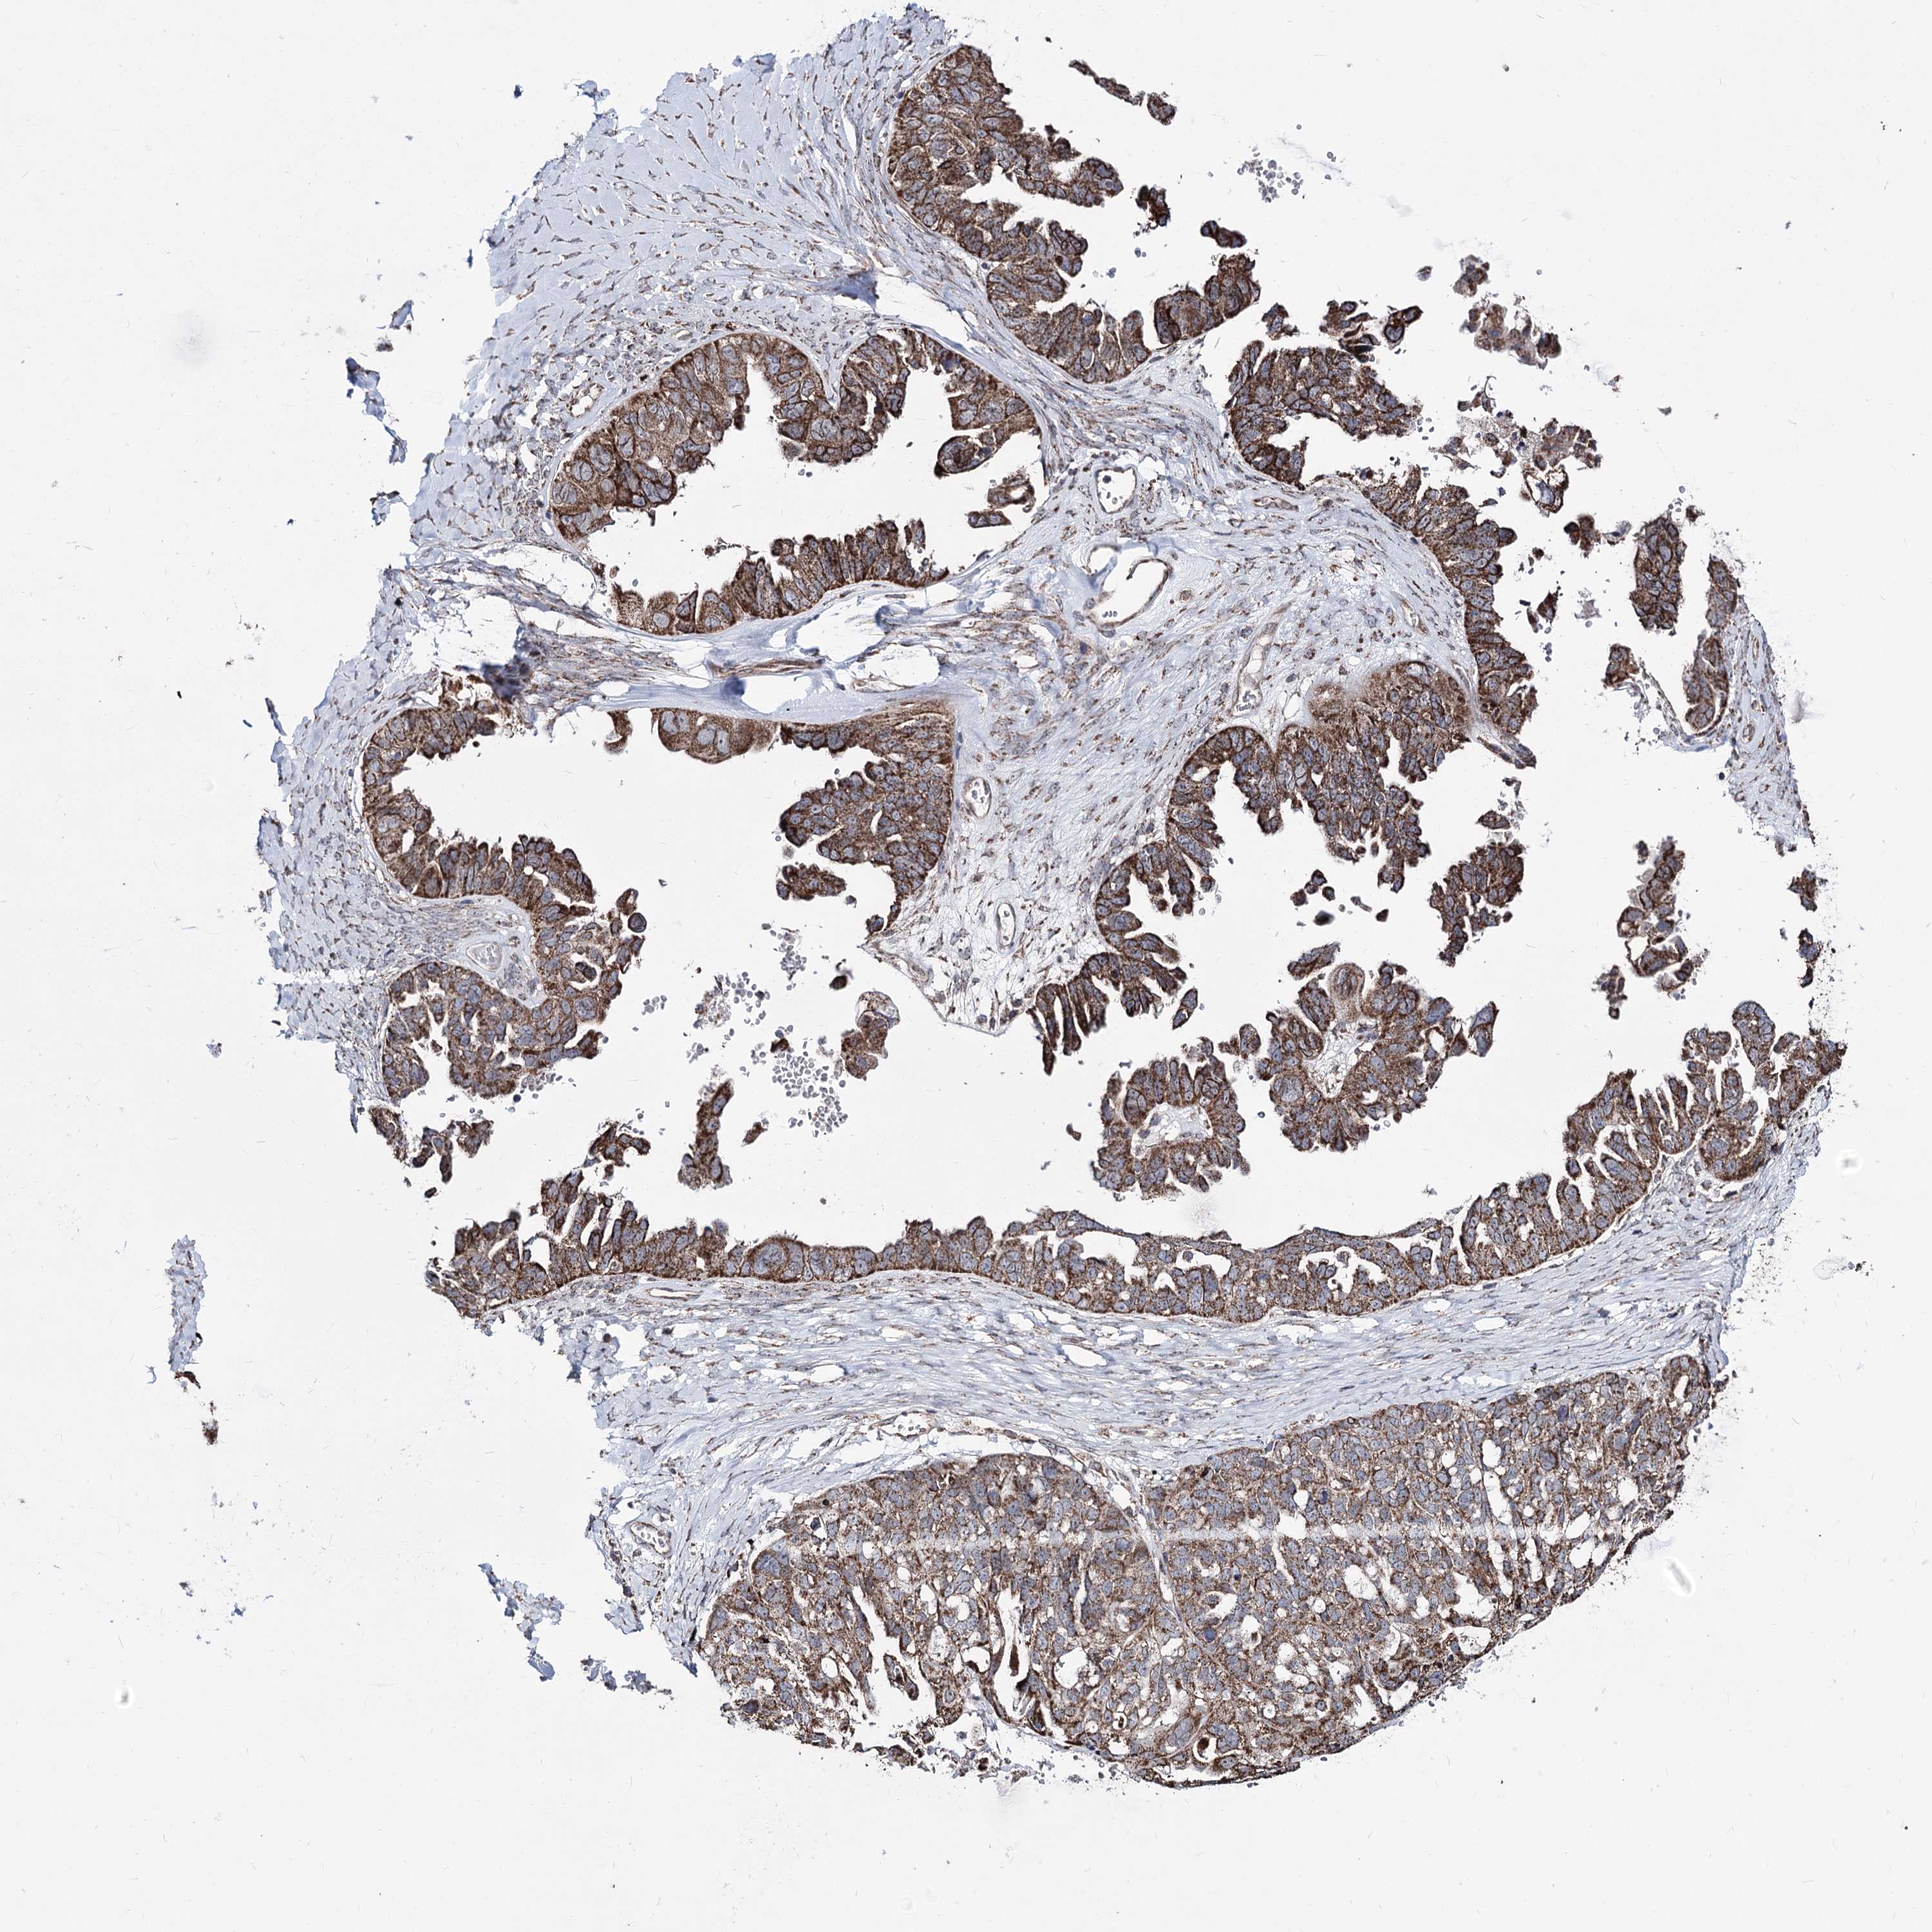

OVARIAN CANCER - Protein expressioni

A mouse-over function shows sample information and annotation data. Click on an image to view it in a full screen mode. Samples can be filtered based on level of antibody staining by selecting one or several of the following categories: high, medium, low and not detected. The assay and annotation is described here.

Note that samples used for immunohistochemistry by the Human Protein Atlas do not correspond to samples in the TCGA dataset.

Antibody stainingi

Antibody staining in the annotated cell types in the current human tissue is reported as not detected, low, medium, or high, based on conventional immunohistochemistry profiling in selected tissues. This score is based on the combination of the staining intensity and fraction of stained cells.

Each image is clickable and will lead to virtual microscopy that enables deeper exploration of all samples and also displays staining intensity scores, fraction scores and subcellular localization as well as patient and tissue information for each sample.

Antibody HPA038122

Staining

High

Medium

Low

Not detected

Intensity

Strong

Moderate

Weak

Negative

Quantity

>75%

75%-25%

<25%

None

Location

Nuclear

Cytoplasmic/membranous

Cytoplasmic/membranous,nuclear

Cystadenocarcinoma, serous, NOS

Carcinoma, endometroid

Cystadenocarcinoma, mucinous, NOS

Carcinoma, NOS